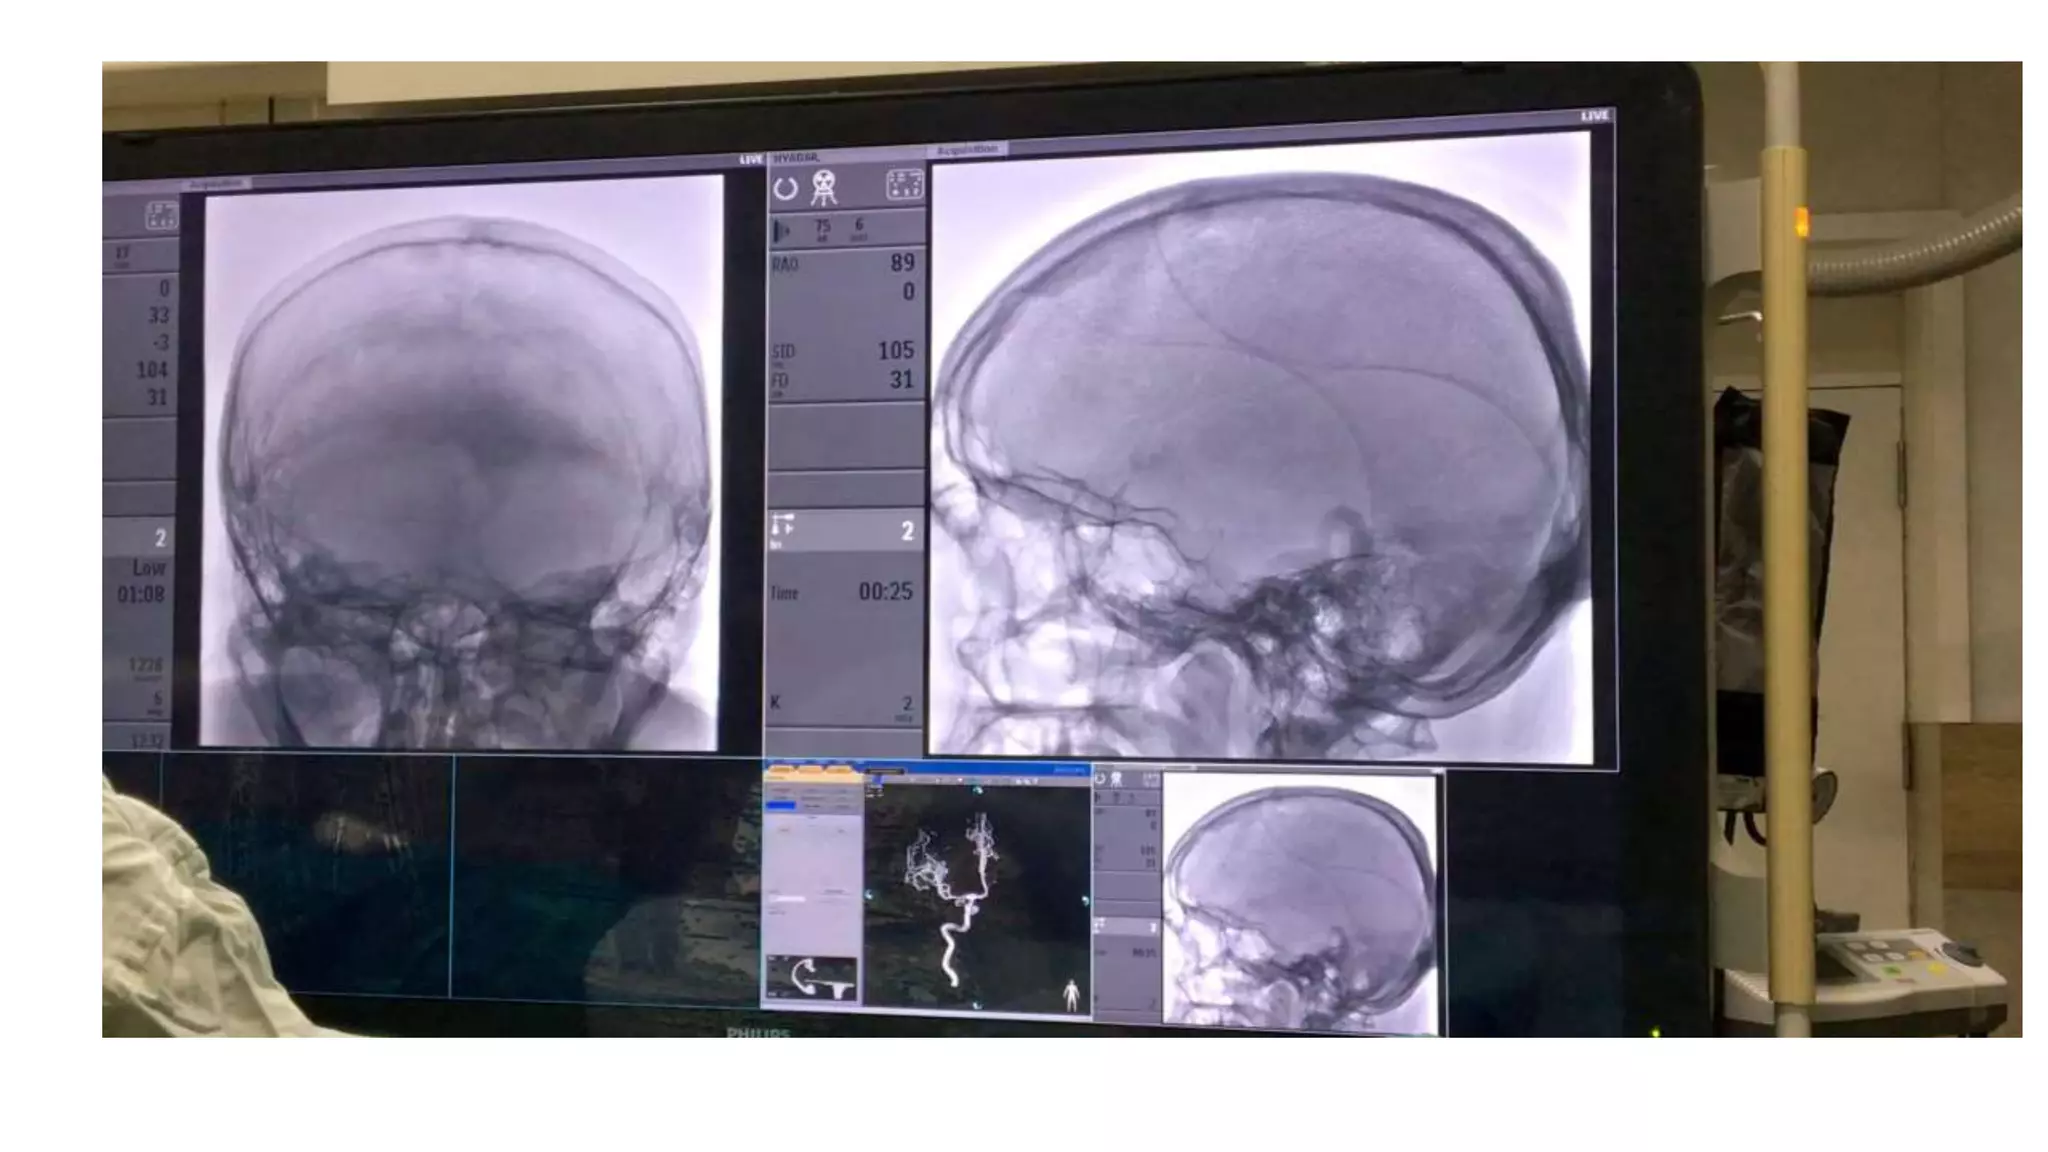

Video